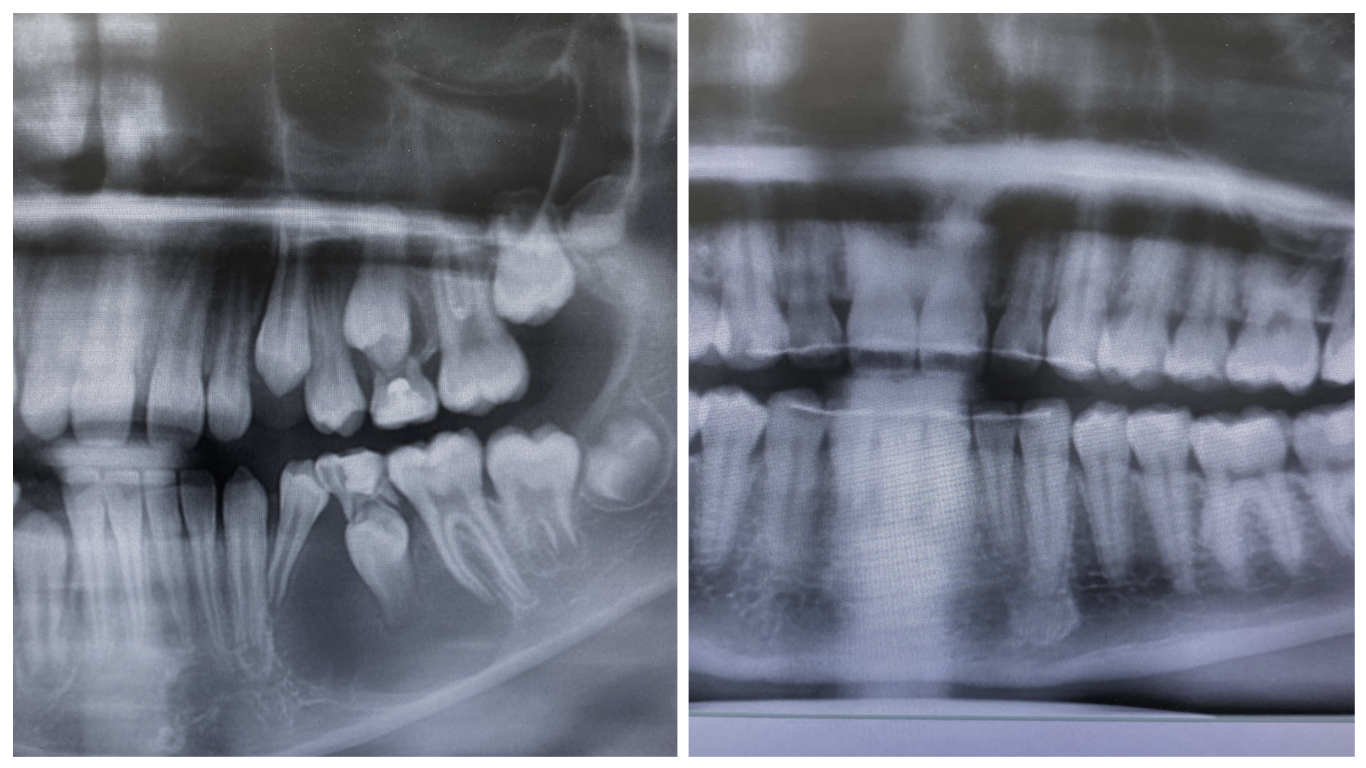

Вот смотрите, верхняя стрелка показывает на молочный зуб. Ниже стоматолог одной клиники на прицельном рентгене увидел нечто непонятное. Стали разбираться. На КТ увидели довольно обширную полость в костной ткани. Это киста — пузырь жидкости, давящий на окружающие ткани. Проблема в том, что эта киста росла несколько лет, и кость челюсти стала тонкой, как спичка. И сломаться она готова буквально от морковки или удара веткой.

Вот так выглядит эта навигация:

Но когда нам нужно добавить фото пациенту на аватарку или когда мы объясняем самому пациенту, что происходит, используется развёртка этого рулона в плоскость. Получается что-то вроде плоской карты мира вместо глобуса. Причём карта мира делается на глубине 13 миллиметров. Обычно как раз там находится всё самое интересное.

Итак, это 13-миллиметровый срез через толщу челюсти. Возможно, вы запоминаете людей в лица. Мы, стоматологи, запоминаем вас вот в такие 13-миллиметровые срезы.

Вот было-стало:

Как видите, в итоге пациент в порядке. Прекрасная медицинская находка, которая спасла ребёнка от серьёзной проблемы.